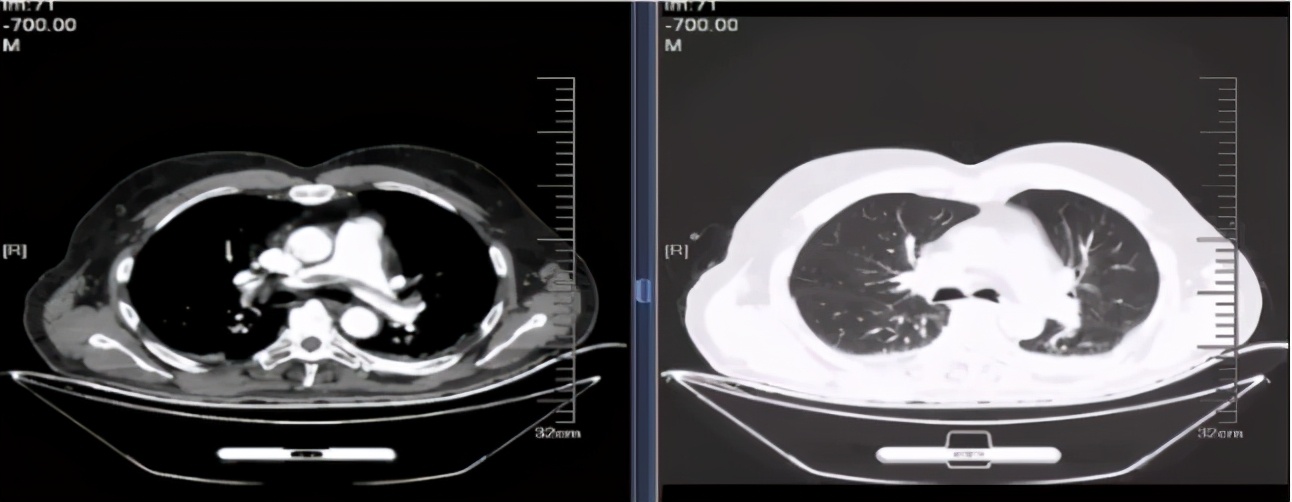

肺CT: